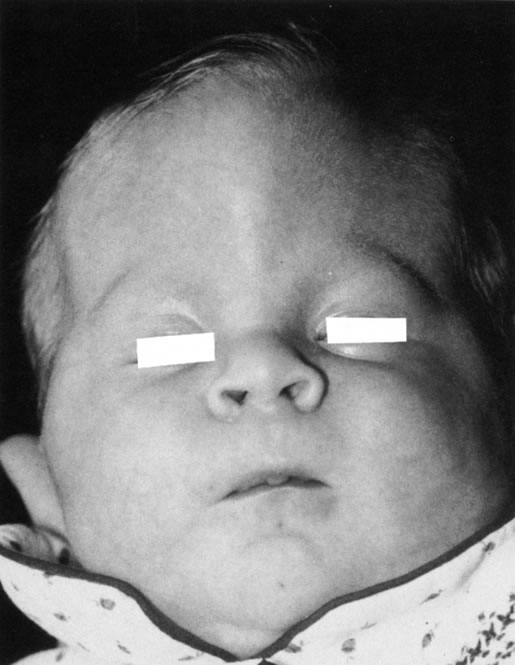

Anophthalmos and microphthalmos are usually unilateral and may be associated with a variety of craniofacial and systemic anomalies, including orbital hypoplasia, facial clefts, basal encephalocele, hemifacial microsomia, mandibulofacial dysostosis, cardiac anomalies, polydactyly, and mental retardation. When they occur unilaterally, they also can be associated with anomalies of the contralateral “normal” eye, including cataract, cornea1 opacities, microphthalmos, coloboma, epibulbar dermoids, and nystagmus. Anophthalmos and severe microphthalmos frequently are associated with contracted conjunctival fornices, phimotic eyelids, and generalized hypoplasia of the periocular soft tissues (Fig. 1). When soft tissue contractures occur, the early use of conformers is essential to expand these tissues.2 This treatment should be instituted in the first month of life, with progressive enlargement of the conformer over time to achieve maximum expansion of the conjunctival fornix. Unfortunately, this treatment usually does not stimulate adequate orbital bone growth, and unilateral microphthalmos and anophthalmos may be associated with secondary orbital hypoplasia (Fig. 2). Serial implantation of progressively larger orbital implants or placement of expansile orbital implants has been advocated to stimulate bony orbital development.3,4